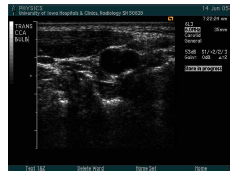

what are the arrows pointed to? what approach is being used?

trans CCA prox